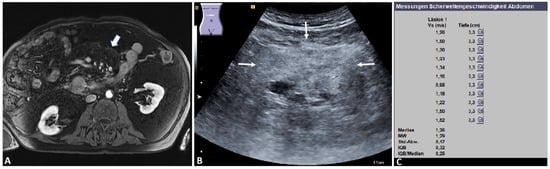

| Mesenteric fat bulk | 8 | 0.90 ± 0.24 | 0.67 | 1.35 | 5.43 ± 1.65 |